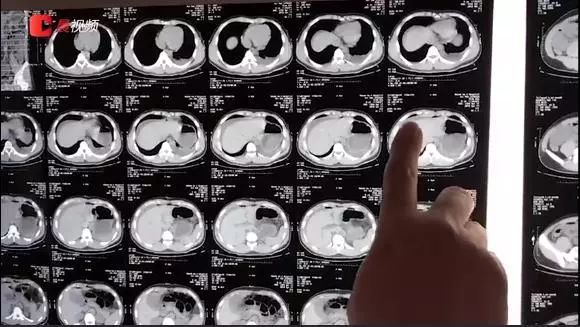

医院CT检查结果显示,患者腹腔内大量积液,肝脏脾脏周围都是积液,积液密度较高。同时,患者血红蛋白指数下降,可能有出血或贫血的情况。

很快患者被送入手术室,普外科医生在手术过程中发现,在脾脏横结肠以及胰尾、脾结肠韧带发现一个圆形的三厘米左右的血肿,胰腺尾部和横结肠也同时撕裂。手术中,血肿还在不停的往外渗血,出血量高达2600毫升(正常人血量为5000毫升),出血量超过全身总血量的一半。